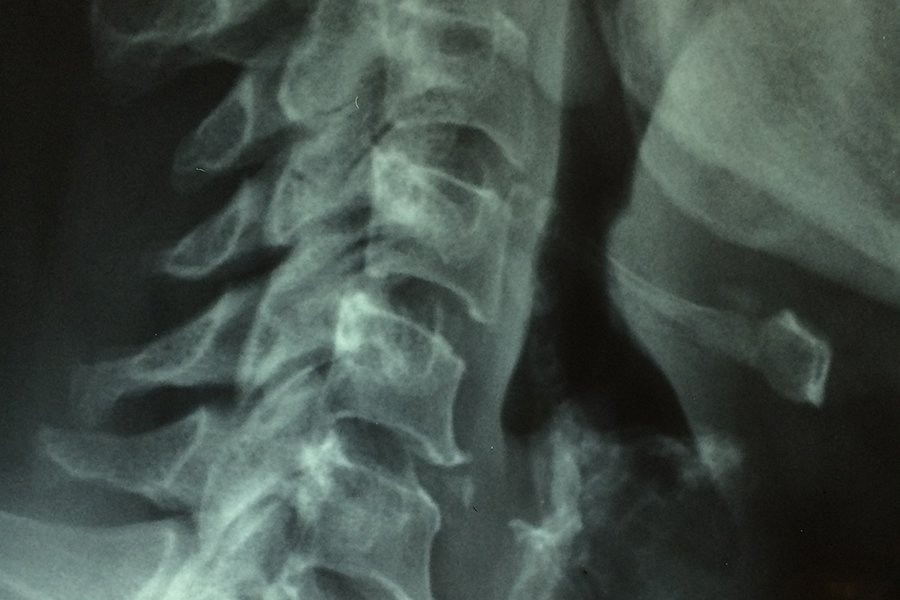

Новое исследование показывает, что образование рубцов после травм спинного мозга является более сложным процессом, чем считалось ранее. Ученые определили два типа периваскулярных клеток, которые играют ключевую роль в формировании рубцовой ткани, которая препятствует регенерации нервов и функциональному восстановлению. Эти результаты, опубликованные в журнале Nature Neuroscience, также актуальны для других травм головного и спинного мозга и могут привести к разработке таргетной терапии для уменьшения рубцов и улучшения результатов.

Центральная нервная система (ЦНС) имеет очень ограниченные способности к исцелению. Травмы в результате дорожно-транспортных происшествий, спортивных инцидентов или аутоиммунных заболеваний, таких как рассеянный склероз, часто приводят к постоянным функциональным нарушениям. Независимо от причины травмы, организм реагирует формированием границы вокруг поврежденной ткани, которая в конечном итоге становится постоянной рубцовой тканью.

Хотя рубцовая ткань запечатывает поврежденный участок, она также предотвращает функциональное восстановление. После травм спинного мозга рубцовая ткань блокирует регенерацию нервных волокон, соединяющих головной мозг с телом, что приводит к параличу после тяжелых травм.

Исследовательская группа под руководством Кристиана Гёрица из Каролинского института добилась значительного прогресса в понимании того, как формируется рубцовая ткань в ЦНС. В настоящее время группа определила два различных типа периваскулярных клеток, которые выстилают различные части кровеносных сосудов и являются основными факторами, способствующими образованию фиброзной рубцовой ткани после травмы спинного мозга. В зависимости от местоположения поражения два идентифицированных типа клеток вносят разный вклад.